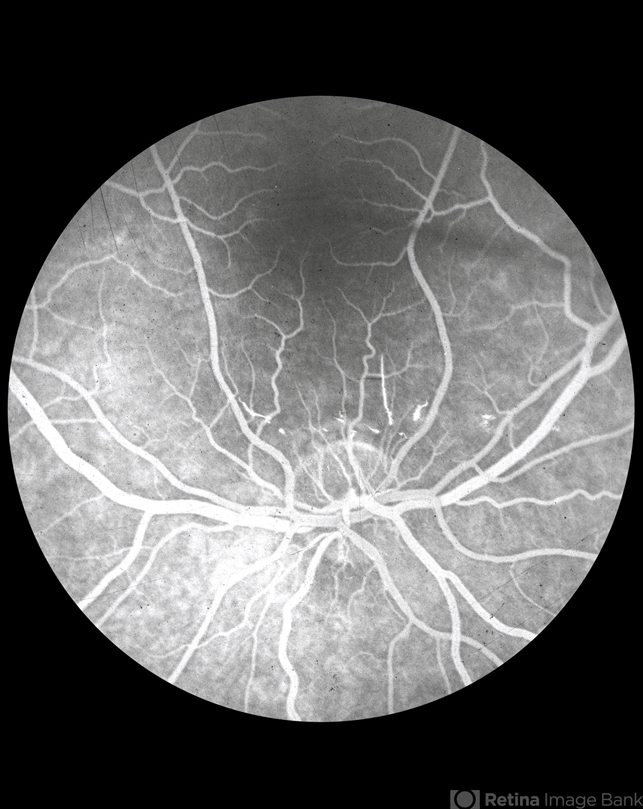

- disc drusen, peripapillary subretinal new vessel membrane

- No history or color photos. Fluorescein angiogram sequence.